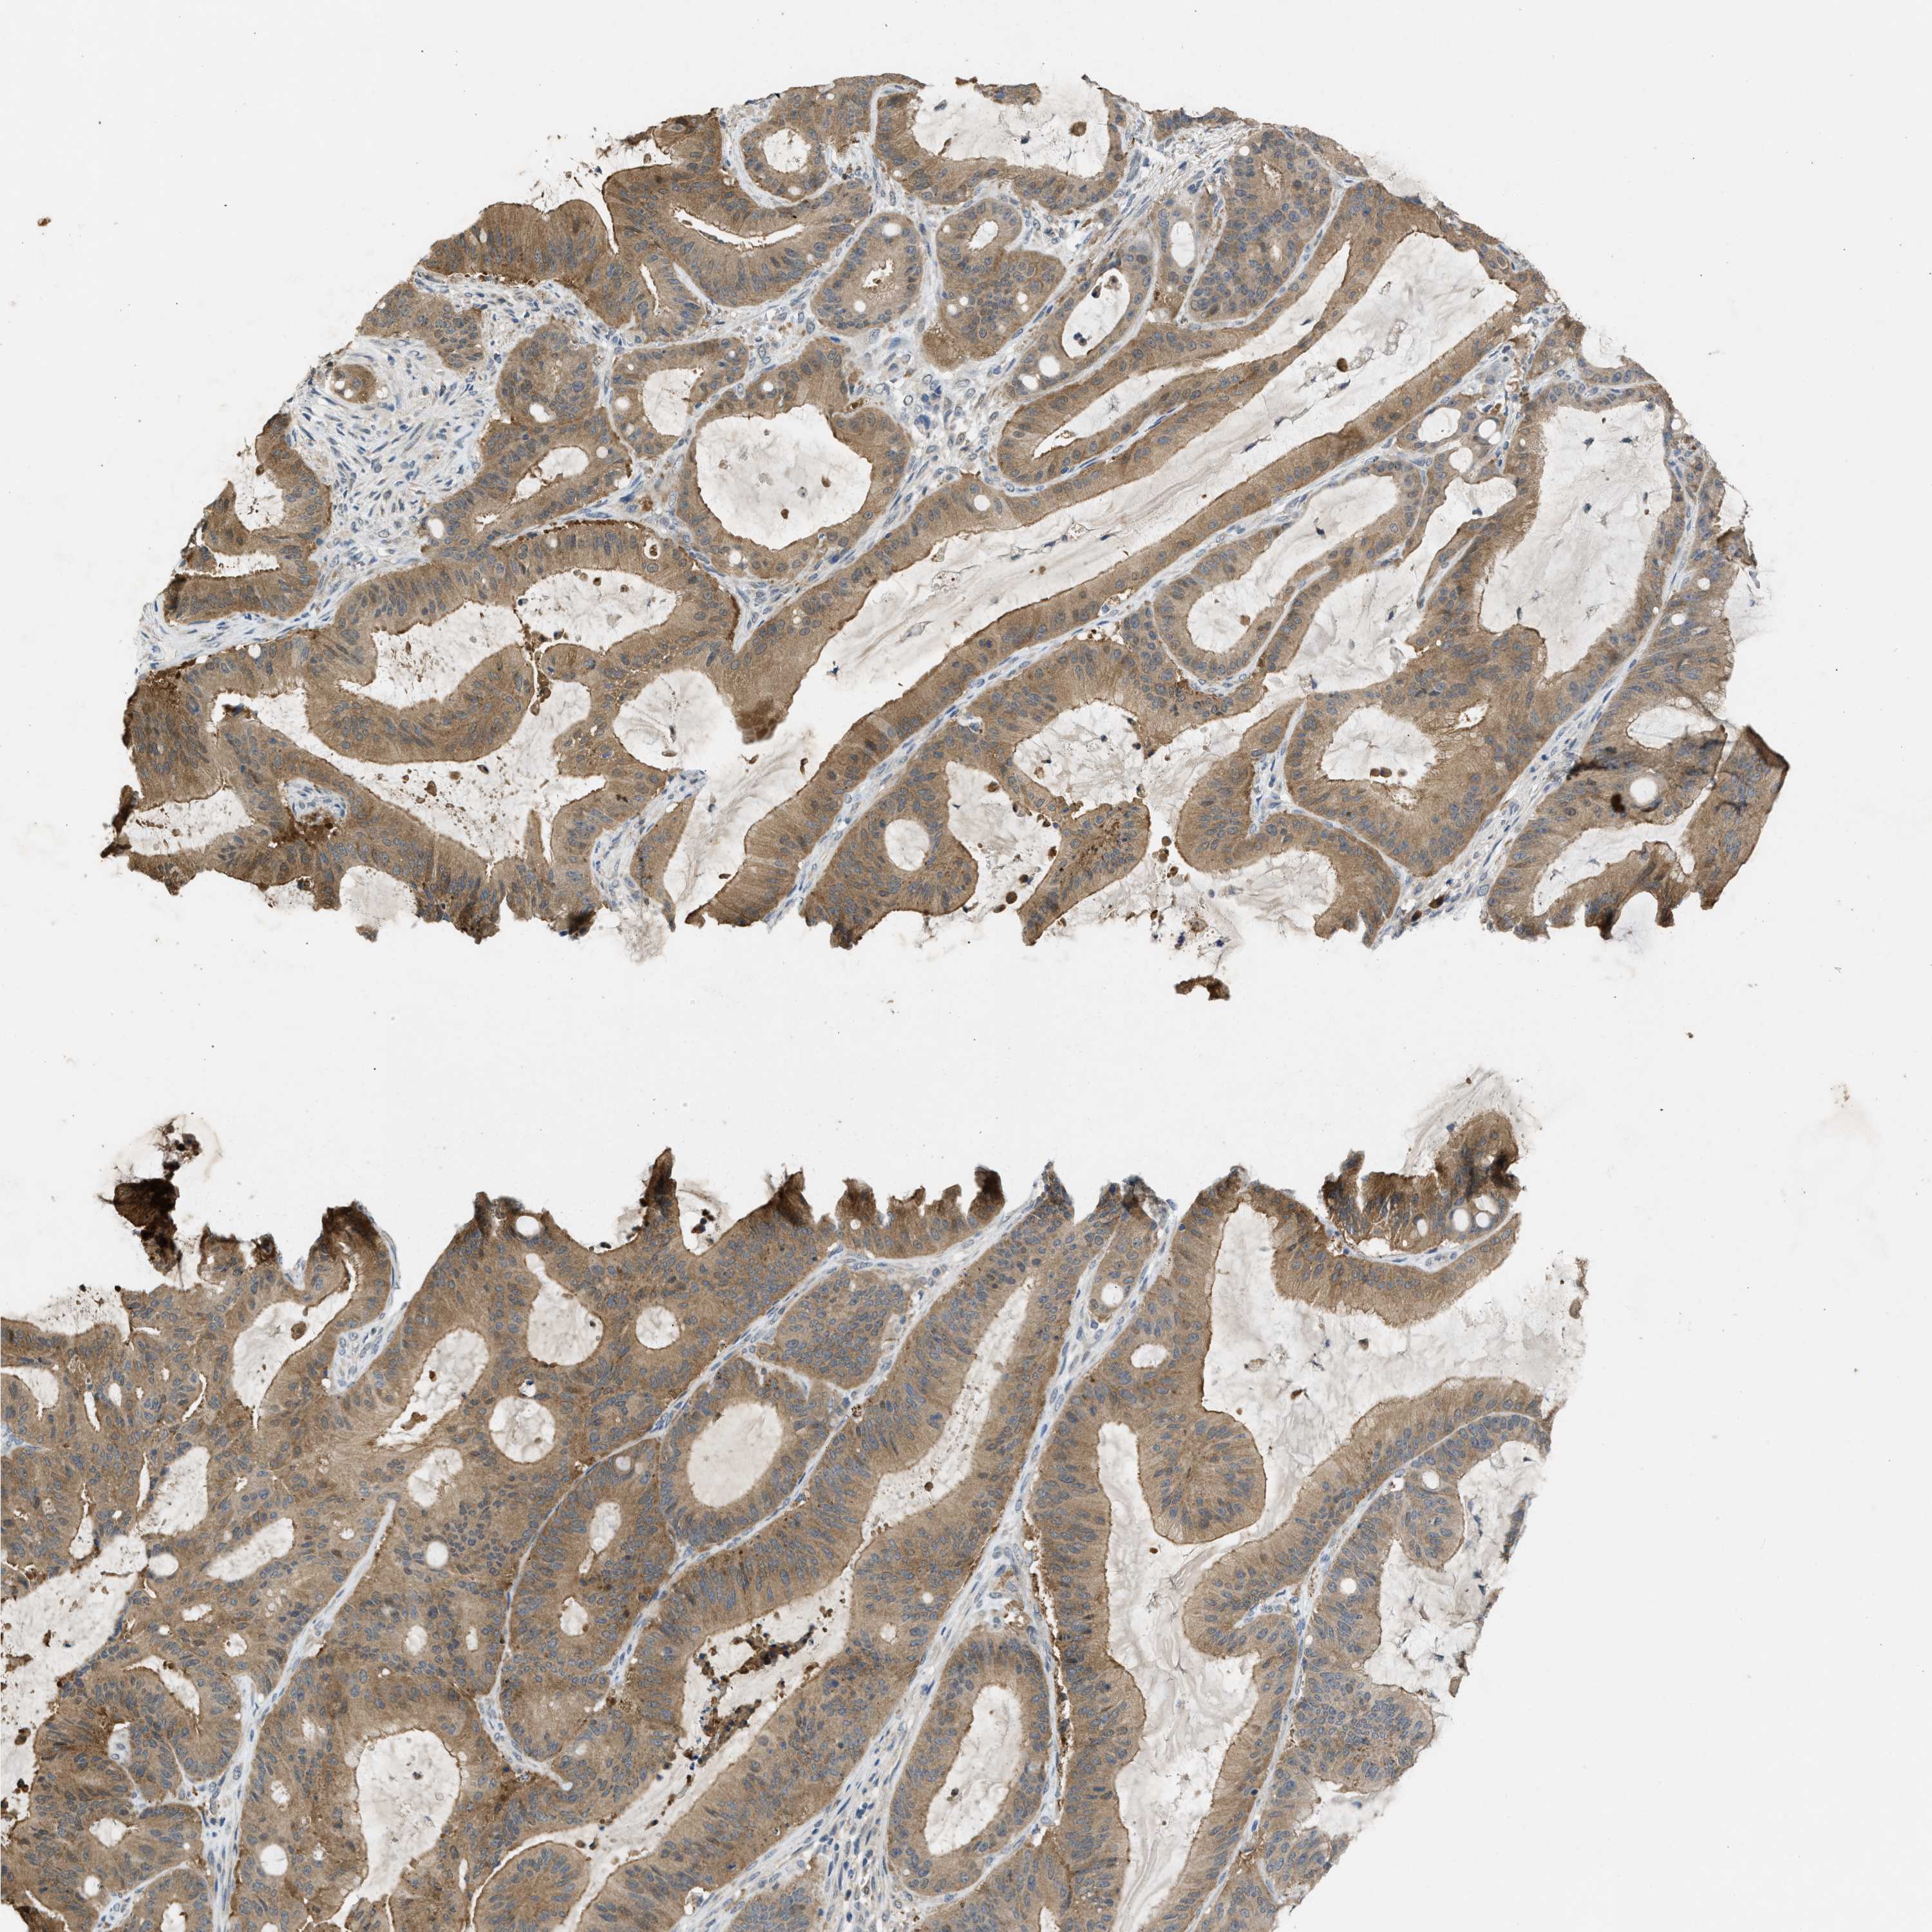

LIVER CANCER - Protein expressioni

A mouse-over function shows sample information and annotation data. Click on an image to view it in a full screen mode. Samples can be filtered based on level of antibody staining by selecting one or several of the following categories: high, medium, low and not detected. The assay and annotation is described here.

Note that samples used for immunohistochemistry by the Human Protein Atlas do not correspond to samples in the TCGA dataset.

Antibody stainingi

Antibody staining in the annotated cell types in the current human tissue is reported as not detected, low, medium, or high, based on conventional immunohistochemistry profiling in selected tissues. This score is based on the combination of the staining intensity and fraction of stained cells.

Each image is clickable and will lead to virtual microscopy that enables deeper exploration of all samples and also displays staining intensity scores, fraction scores and subcellular localization as well as patient and tissue information for each sample.

Antibody CAB018561

Staining

High

Medium

Low

Not detected

Intensity

Strong

Moderate

Weak

Negative

Quantity

>75%

75%-25%

<25%

None

Location

Nuclear

Cytoplasmic/membranous

Cytoplasmic/membranous,nuclear

Cholangiocarcinoma

Carcinoma, Hepatocellular, NOS